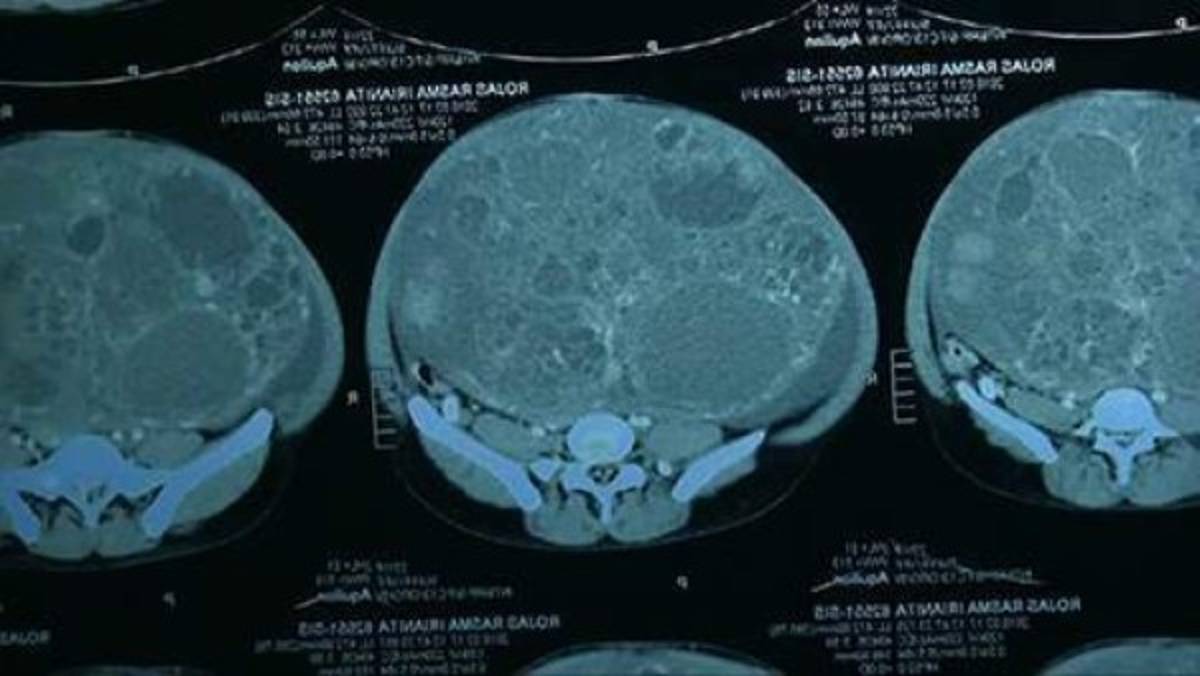

Un tumor de 16 kilos le fue extraído a una mujer de 22 años de edad por un equipo de médicos especialistas en Perú.

De acuerdo al informe medico, el tumor estuvo creciendo durante más de ocho años, y parecía que la joven, Iranita Rojas, estaba embarazada.